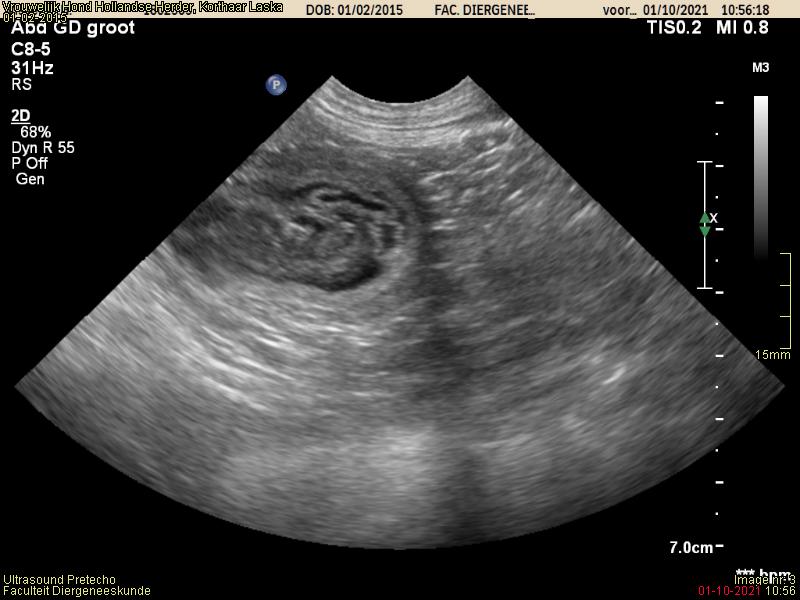

Echo Akyra

Vandaag een drachtecho gehad van Akyra.

Het mag duidelijk zijn dat Akyra drachtig is! We verwachten de pups begin April.